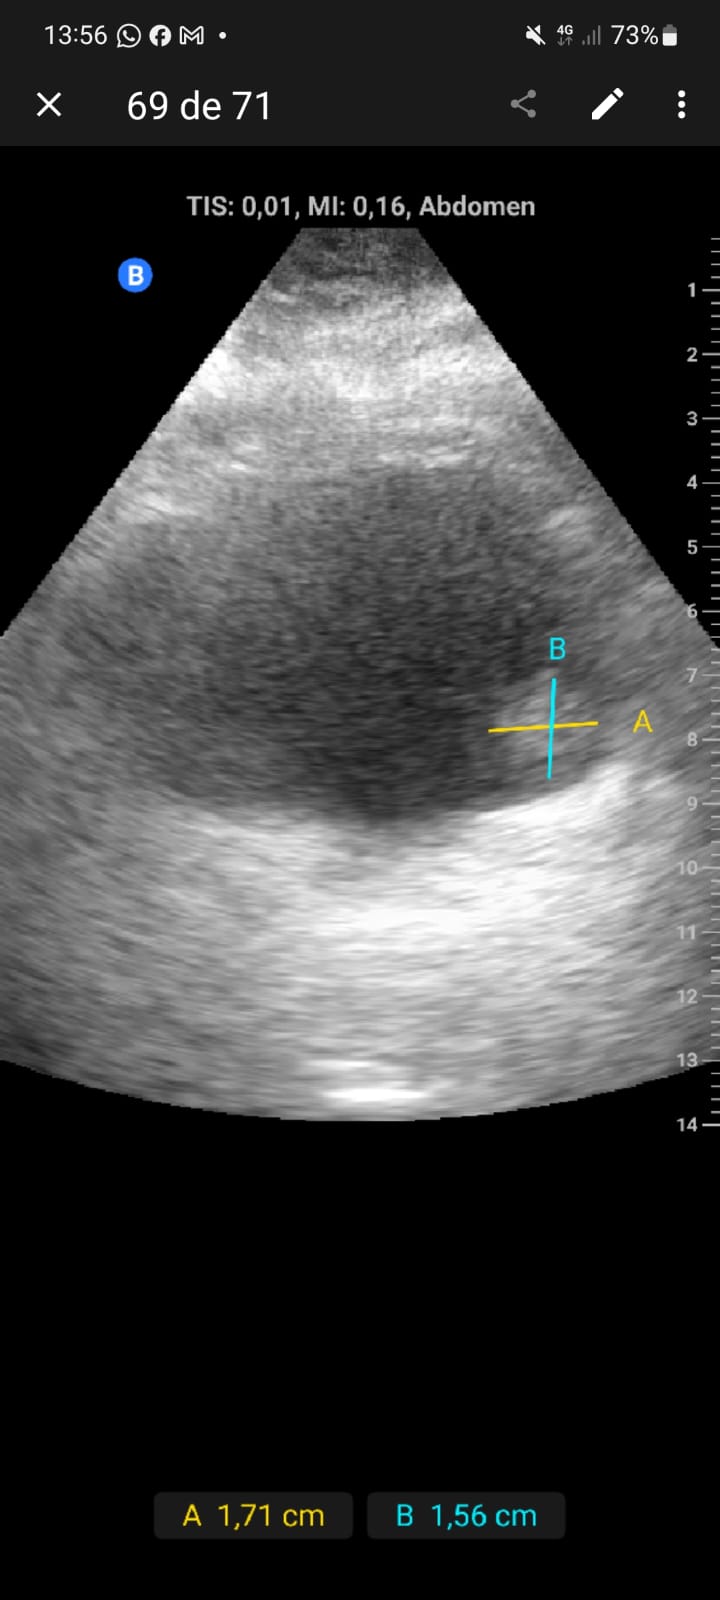

Exfumador, HTA, hipercolesterolemia, cirrosis hepática por alcohol. Hombre de 58 años que refiere episodio de hematuria macroscópica hace dos semanas, coincidiendo con un esfuerzo físico intenso el día previo. No presenta disuria, fiebre, poliaquiuria, ni dolor. En controles posteriores, no había recurrencia de hematuria y el paciente se encontraba asintomático.Exploración física sin hallazgos relevantes. Ecografía realizada en consulta en apenas 5 minutos mostró una masa en la cara lateral izquierda de la vejiga, de 1,5 x 1,3 cm, con características sugerentes de lesión tumoral superficial.

Descripción de los hallazgos ecográficos y las imágenes más relevantes para la resolución del caso

Lesión sólida, pediculada, de bordes definidos y fronda larga en la cara lateral izquierda de la vejiga.

Se sospechó un tumor vesical; pólipo vesical. Urología confirmó la lesión mediante cistoscopia, describiendo una masa papilar superficial de 2 cm en la pared lateral izquierda.